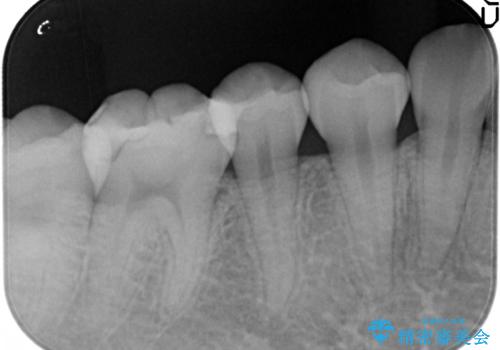

- むし歯の治療を希望されて来院された患者様です。

セラミックインレーによる修復を行っております。

保険治療で使える材料には制限があり、見た目だけでなく精度でも劣ります。当院でのセラミックインレーは歯とのつなぎ目を拡大鏡で確認して精度高く仕上げるため、むし歯のリスクを限りなく少なくできるよう治療します。